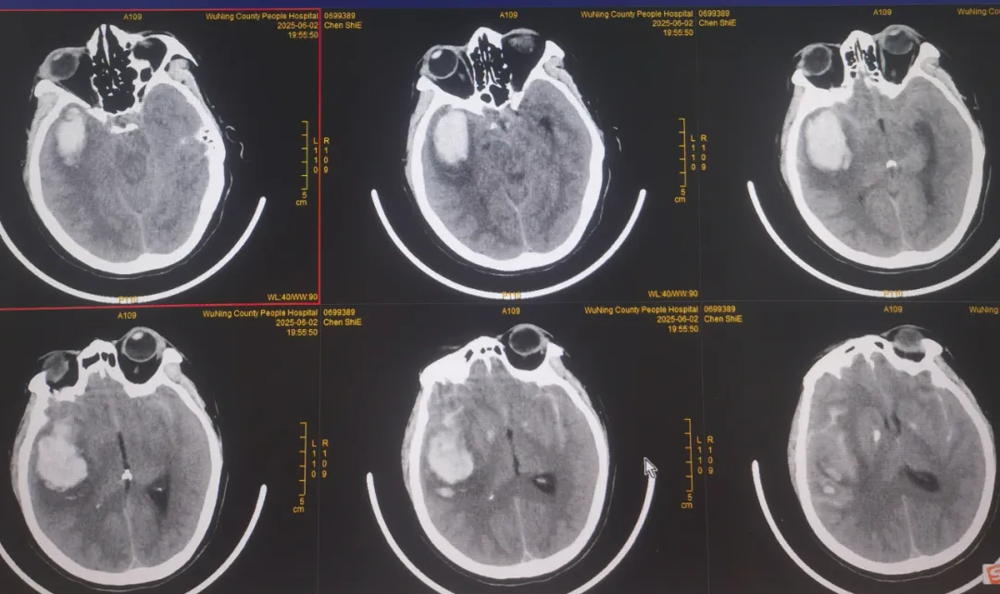

近日,武宁县总医院人民医院院区神经外科团队顺利完成了我县首例破裂脑动脉瘤夹闭手术,患者术后情况良好,恢复效果理想。

脑动脉瘤夹闭借助高清晰显微镜下操作,手术难度高、风险大,以往此类患者只能转诊上级医院。人民医院院区神经外科团队凭借扎实的专业功底迎难而上,精准操作,成功拆除患者颅内"不定时炸弹"。这一突破填补了我县在脑动脉瘤治疗领域的技术空白。

近年来,武宁县总医院人民医院院区神经外科团队借力与湘雅医院江西医院紧密型医联体东风,展现出蓬勃向上的发展势头,多项高难度诊疗技术日臻成熟:微创神经内镜技术、显微镜下脑内血肿清除术、脑膜瘤切除术以及复杂重型颅脑创伤救治能力实现突破性提升。此次脑动脉瘤夹闭手术成功实施,在县域神经外科领域书写了新的篇章,实现了“零”的突破。